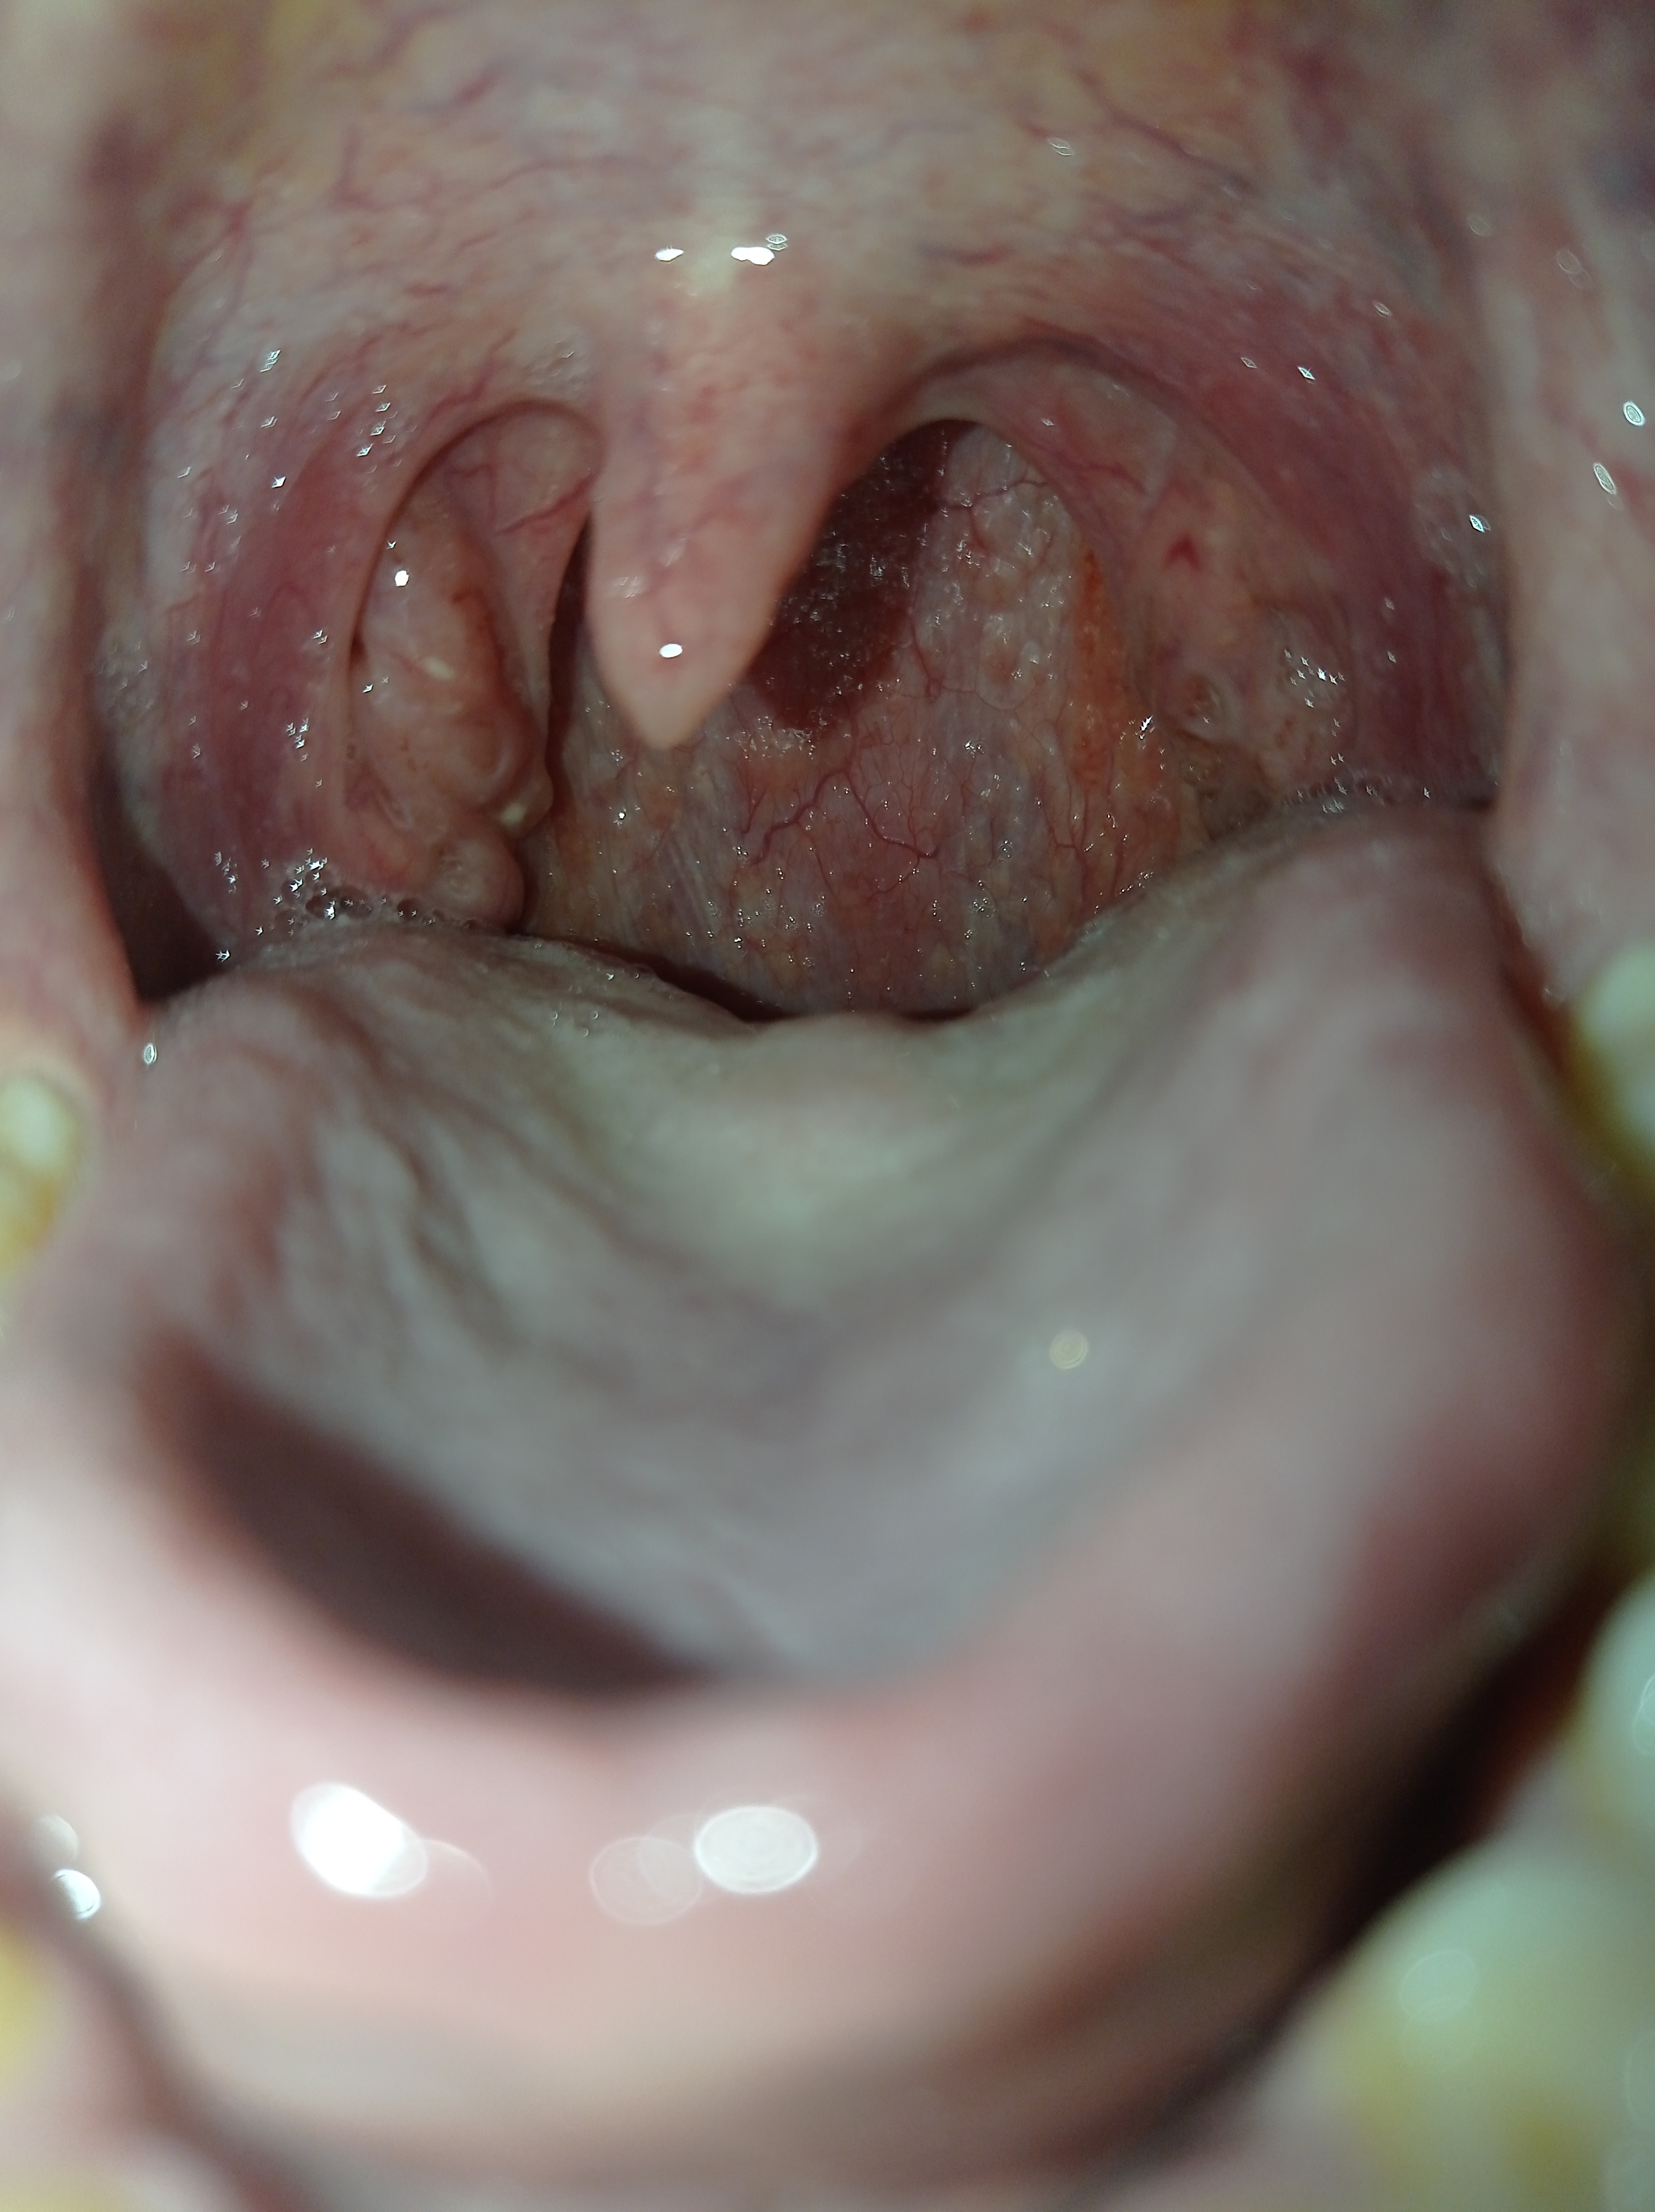

Фарингита -тред. Горло красное всегда, глаза побаливают, отëчность, под челюстью узлы немного непр